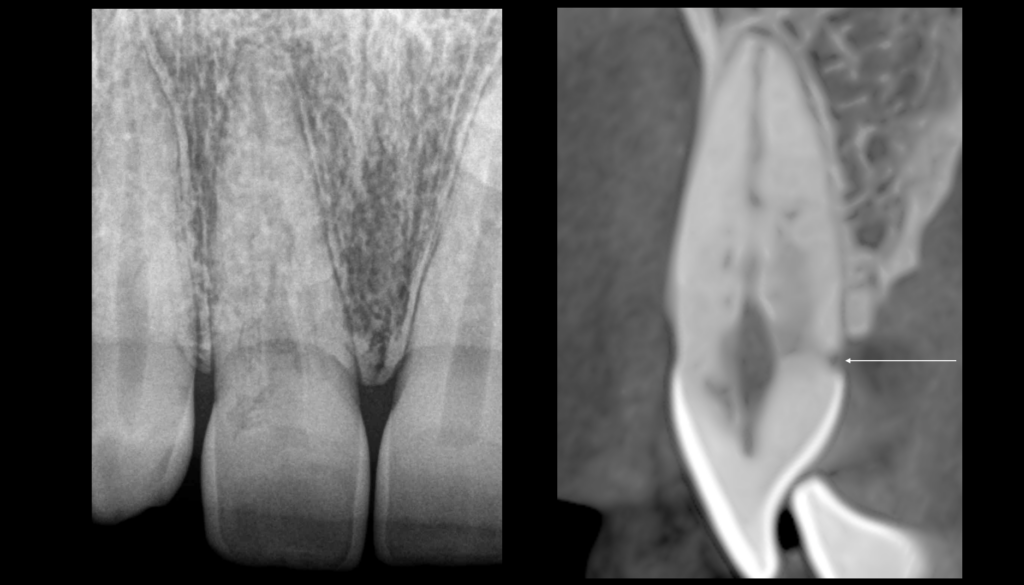

🦷 𝐋𝐞𝐬 𝐫𝐞́𝐬𝐨𝐫𝐩𝐭𝐢𝐨𝐧𝐬 𝐫𝐚𝐝𝐢𝐜𝐮𝐥𝐚𝐢𝐫𝐞𝐬 𝐜𝐞𝐫𝐯𝐢𝐜𝐚𝐥𝐞𝐬 𝐞𝐱𝐭𝐞𝐫𝐧𝐞𝐬 𝐨𝐧𝐭 𝐮𝐧𝐞 𝐩𝐨𝐫𝐭𝐞 𝐝’𝐞𝐧𝐭𝐫𝐞́𝐞, 𝐝𝐚𝐧𝐬 𝐥𝐞 𝐜𝐞́𝐦𝐞𝐧𝐭, 𝐬𝐨𝐮𝐬 𝐥’𝐚𝐭𝐭𝐚𝐜𝐡𝐞 𝐞́𝐩𝐢𝐭𝐡𝐞́𝐥𝐢𝐚𝐥𝐞.